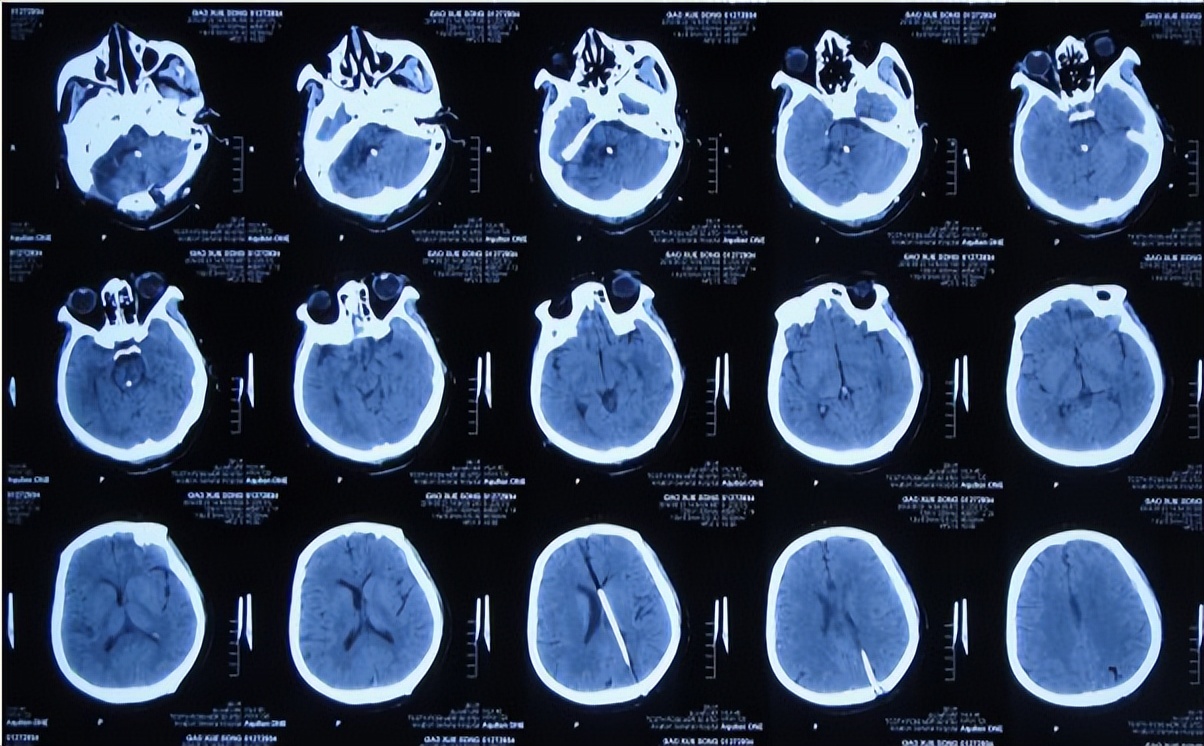

听神经瘤切除术后7天即2013年11月21日,查头颅CT示仍有血肿(图-3),出现发热,最高体温体温38.3 ℃左右,给予腰穿检查脑脊液后认为有感染,给予腰大池引流术及鞘内注射万古霉素。

图-3:2013年11月21日头颅CT

腰大池引流术后12天即2013年12月3日(听神经瘤切除术后19天),期间仍反复发热,查头颅CT示一侧脑室扩张大,硬膜下水肿(图-6),担心加重颅内感染,改行腰穿治疗。

图-6:2013年12月3日头颅CT

听神经瘤切除术后28天即2013年12月12日,查头颅CT示仍有一侧脑室扩张(图-7)。

图-7:2013年12月12日头颅CT

听神经瘤切除术后42天即2013年12月26日,查头颅CT(图-8)后持续交替给予腰大池引流、腰穿治疗并联合鞘内注射。

图-8:2013年12月26日头颅CT